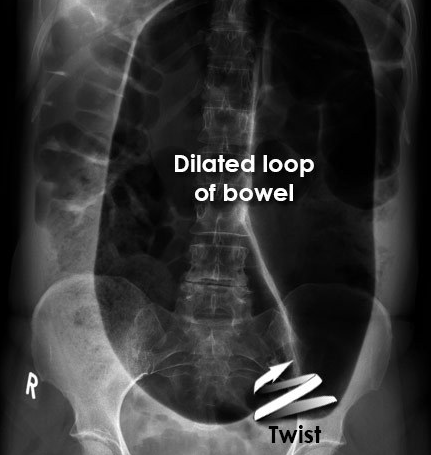

What is the radiological diagnosis?

Sigmoid volvulus

Normal

Ascites

Small bowel obstruction

Pneumoperitoneum

A

Sigmoid volvulus Caecum volvulus

This abdominal X-ray shows the ‘coffee bean’ sign, a loop of large bowel dilatation rising from the pelvis indicating **sigmoid volvulus.**